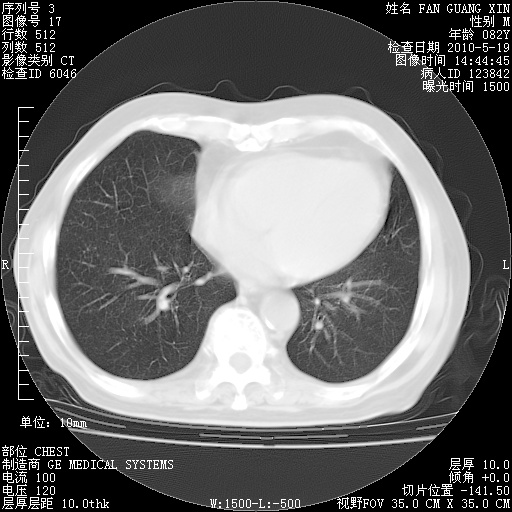

复查肺部CT,明显好转。为什么发热呢?

治疗3周后的肺部CT